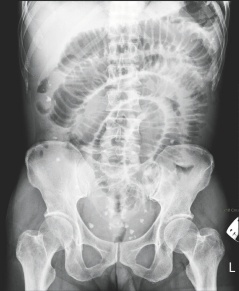

臺南市55歲女子腹中取出29顆大大小小的“蛋”,從X光上可看到腹中滿布點狀的白色物體。

這名女子最近因腹痛、嘔吐而到成大急診就醫(yī),醫(yī)師從X光檢查中,發(fā)現(xiàn)腹腔內(nèi)有許多白點狀的物體,原本以為是糞石或食物堆積在腸道中,經(jīng)緊急開刀,發(fā)現(xiàn)這些物體是在腸子外,而非腸子里,醫(yī)師共取出大大小小共29顆,色白、外形橢圓,很像蛋一般,材質(zhì)卻像橡膠一般有彈性。